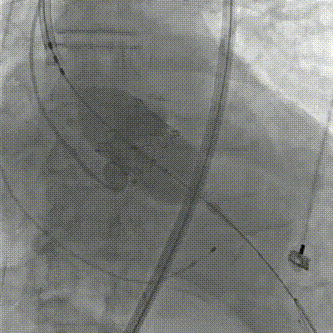

180bpm快速起搏下释放29mm SAPIEN 3瓣膜;

瓣膜释放1

瓣膜释放2

复查造影示人工瓣膜位置,功能,形态良好,左右冠状动脉灌注良好,轻度反流,人工瓣膜植入深度:90/10。TEE显示瓣中无反流,无明显瓣周漏。复查左心室、主动脉收缩压和舒张压分别为125/21mmHg、126/77mmHg;

180bpm快速起搏下释放26mm SAPIEN 3瓣膜;

复查造影示人工瓣膜位置,功能,形态良好,左右冠状动脉灌注良好,未见明显反流及瓣周漏;